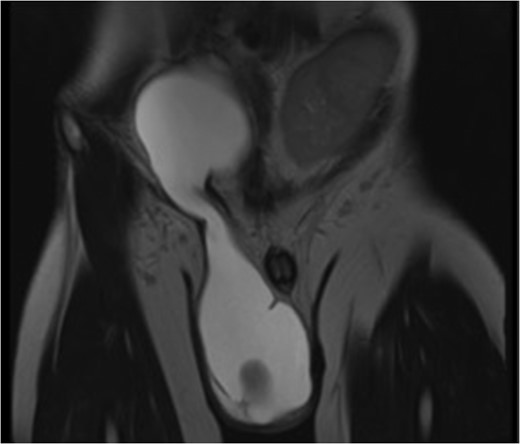

A 24-year-old gentleman, with a kidney transplant, presented with a large right sided scrotal swelling. An MRI pelvis revealed a large right sided hydrocele with a clear communication between the scrotum and peritoneal cavity (Fig. 1). The gentleman was known to have an anterior syringocoele, which was diagnosed antenatally. He suffered with early postnatal renal failure, requiring haemodialysis. He consequently had an initial deceased donor kidney transplant aged 20 months, with the kidney placed in the right retroperitoneal space, and the anastomosis of the transplant renal artery and vein to the aorta and IVC, respectively. He had an open removal of this initial transplant due to recurrent urosepsis via a midline incision. He subsequently underwent a second living donor kidney transplant at 17 years of age.

T2 weighted MRI pelvis (coronal section). MRI pelvis demonstrates a massive communicating ASH/SIR. A characteristic ‘hourglass’ shape is shown, along with the left sided transplant kidney

ASH, or SIR hydrocele, is generally a benign condition. Clinical diagnosis is based on bimanual palpation with the finding of two swellings, abdominal and inguino-scrotal, demonstrating pathognomonic cross fluctuation. Compression of the scrotal swelling may evacuate fluid into the abdominal swelling, and upon release will allow refilling of the scrotal component. This has been named ‘springing back ball’ sign [1]. Ultrasound is used to confirm the clinical findings, and may be useful to delineate other genitourinary pathology. CT or MRI can also be used to confirm initial suspicion, and to demonstrate the classic ASH hourglass shape, as seen in this report, through the inguinal canal.